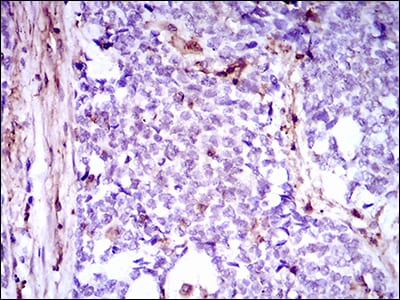

分类: 科研抗体货号: 30505别名: CD146; MUC18应用: WB,IHC,FCM反应种属: Human